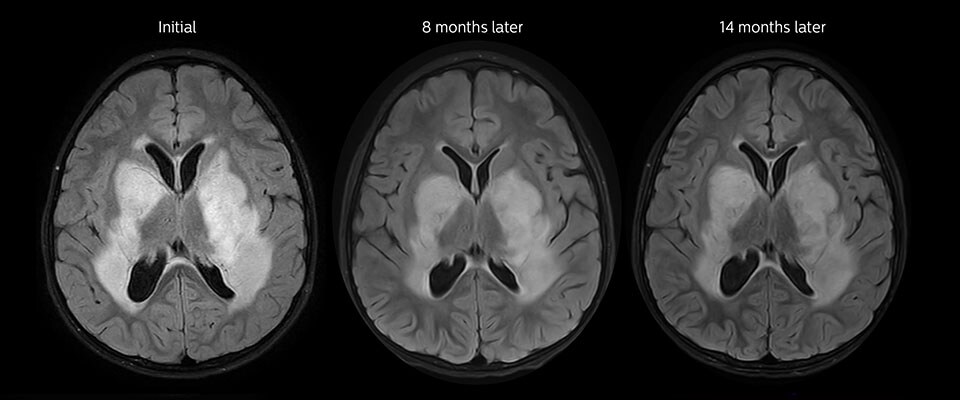

Low-grade glioma in a 5-year-old patient with neurofibromatosis 1. This low-grade lesion does not enhance on the post-contrast images, but does show an intermediate APT signal. The lesion stability over time confirms that it is a low-grade pathology.